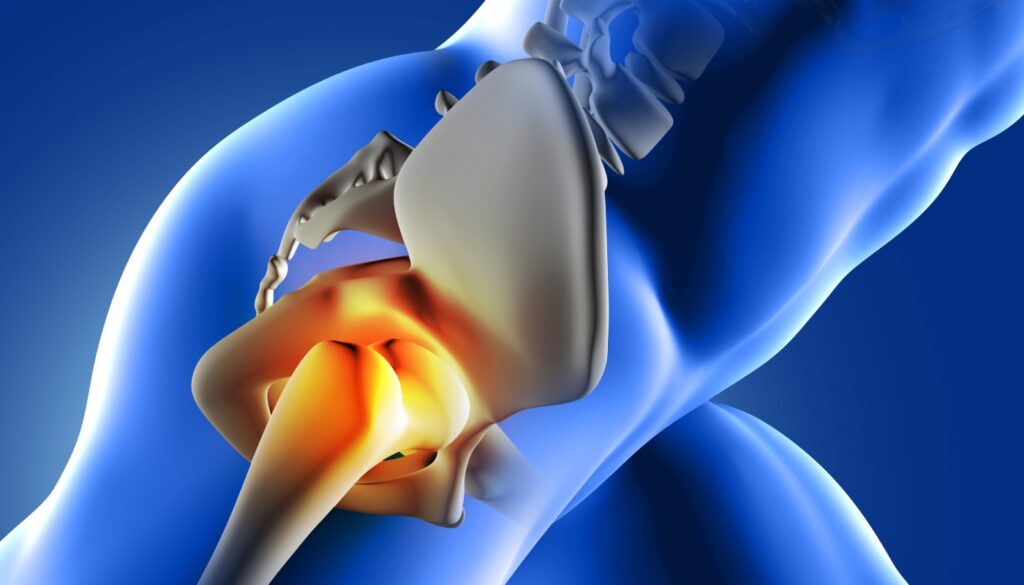

De acordo com informações da Cleveland Clinic, a síndrome do piriforme é uma condição que afeta tanto a parte musculoesquelética do quadril quanto a parte neurológica. Isso se deve ao fato de que o problema começa no músculo piriforme, um músculo profundo da região glútea, mas causa sintomas ao pressionar o nervo ciático, que vai da lombar até os pés.

O piriforme é um músculo que liga a pelve ao fêmur, principal osso da coxa. Ele está envolvido nos movimentos de rotação do quadril e, quando se inflama, tem espasmos ou sofre um estiramento, pode pressionar o nervo ciático. Como esse nervo percorre parte das costas, o quadril e as pernas, os sintomas tendem a se manifestar em uma área extensa.

Estima-se que a doença de Adriane Galisteu seja a causa de apenas 0.3% a 6% dos casos de dor ciática. O diagnóstico da condição pode ser difícil justamente pelas semelhanças com os sintomas de outras condições que também afetam o nervo, como a compressão dele por hérnia de disco, por exemplo.